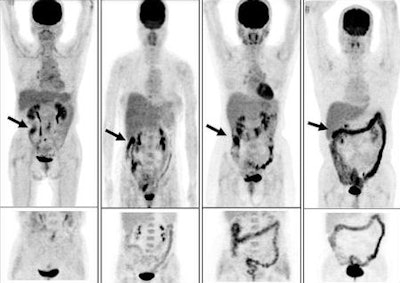

| Initial PET scans (top images) and PET scans obtained at delayed PET/CT after administration of oral laxative-augmented contrast medium (bottom images). The initial PET scans demonstrate colorectal FDG uptake patterns (arrow), as follows: (far left) nodular-focal pattern in ascending colon, (left) segmental pattern in hepatic flexure of colon, (right) nodular-multifocal pattern in colorectum, and (far right) diffuse pattern in transverse and descending colon. Images courtesy of Radiology. |

The analysis showed increased tracer uptake in the colon or rectum at initial PET examination in 138 (16%) of the 847 patients. The 138 patients underwent delayed PET/CT after administration of laxative-augmented contrast medium. Of the 709 patients who did not undergo delayed PET/CT after laxative-augmented contrast administration, 38 subjects were lost to follow-up.

In addition, the researchers identified 24 true-positive findings, 74 true-negative findings, 31 false-positive findings, and eight false-negative findings with FDG-PET. With delayed PET/CT, there were 31 true-positive findings, 97 true-negative findings, nine false-positive findings, and no false-negative findings.

The accuracy of initial PET was 72% (98 of 137 patients), while the accuracy of delayed PET/CT was 93% (128 of 137 patients).